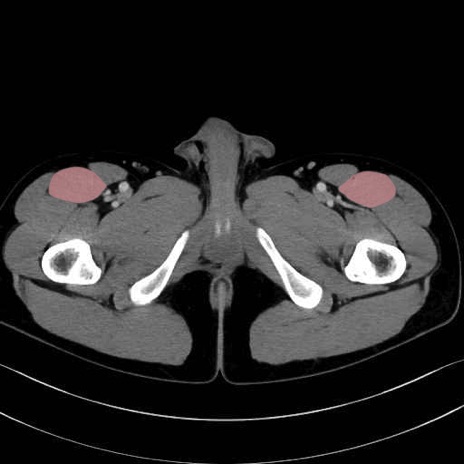

6. 大腿内側(内転筋群)

恥骨筋 (Pectineus)

長内転筋 (Adductor longus)

短内転筋 (Adductor brevis)

大内転筋・小内転筋 (Adductor magnus / Adductor minimus)